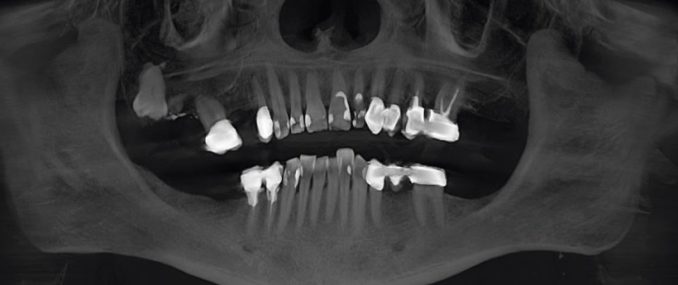

In issue 1-2022 of the magazine ceramic implants, Dr Johann Lechner is featured with a technical article on the topic of “Dental implants and bone marrow defects – Evaluation of […]

In issue 2-2021 of the magazine ceramic implants, Dr Johann Lechner is featured with a technical article on the topic of “Measuring bone density by intra-oral ultrasound for secure implant […]